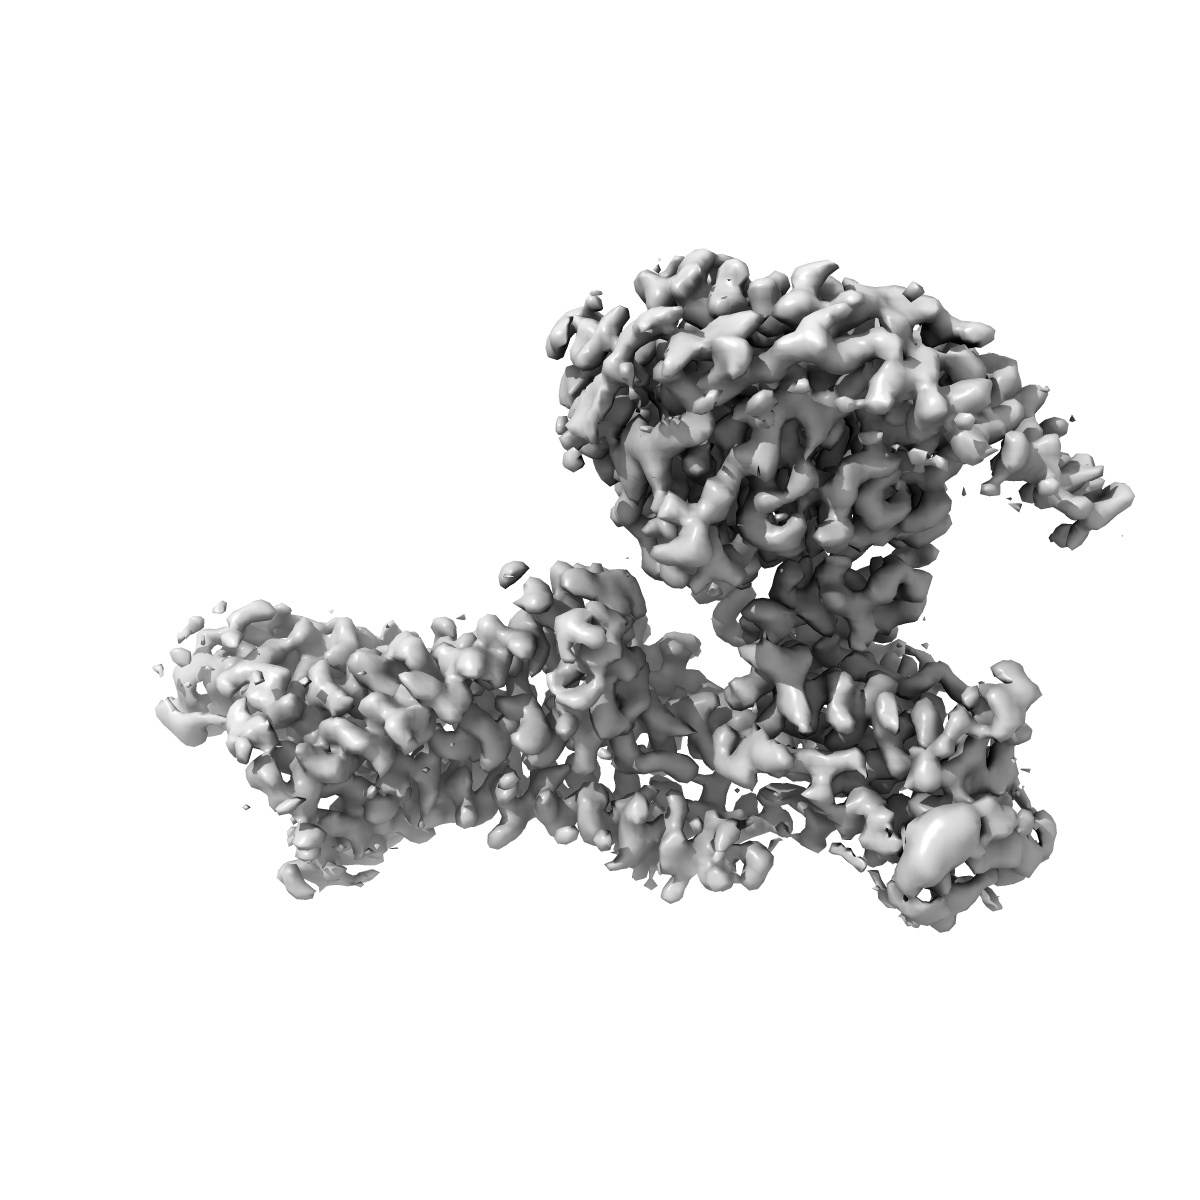

EMD-23281

Cryo-EM structure of the human adenosine A1 receptor-Gi2-protein complex bound to its endogenous agonist

Single-particle3.3 Å

Sample: Human adenosine A1 receptor-Gi2-protein complex bound to its endogenous agonist adenosine